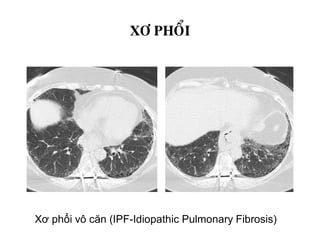

DAÏNG ÑÖÔØNG

XÔ PHOÅI

Xơ phổi vô căn (IPF-Idiopathic Pulmonary Fibrosis)

BEÄNH PHOÅI MOÂ KEÕ

XÔ PHOÅI VOÂ CAÊN (IPF)